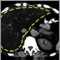

Liver cirrhosis, CT scan